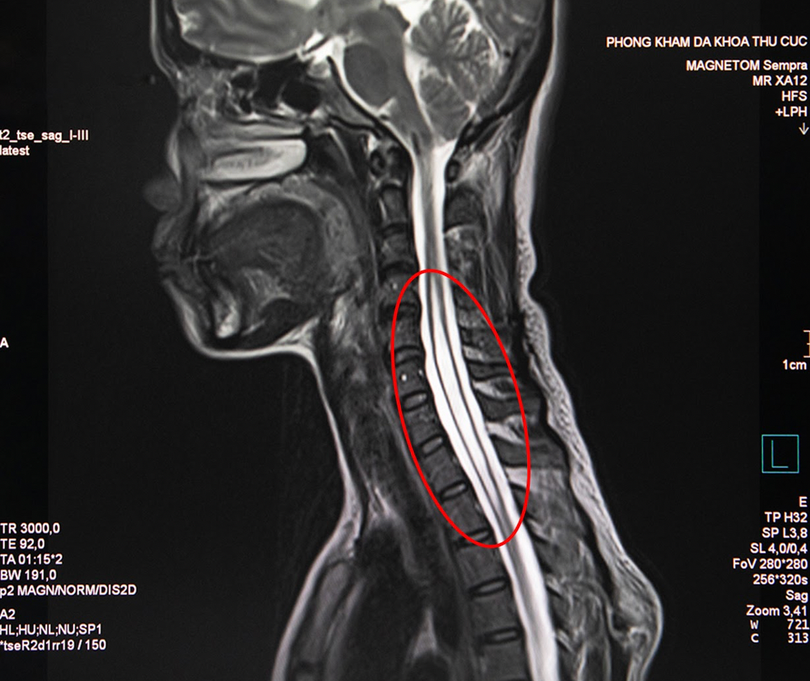

Để tìm hiểu rõ nguyên nhân, BS. Vũ Hải Yến – chuyên gia Nội Thần kinh của Phòng khám - đã chỉ định cho chị H. chụp cộng hưởng từ (MRI) và kết quả cho thấy trong đoạn tủy sống của chị H. từ khu vực cột sống cổ gáy đến giữa lưng hình thành hốc rỗng chứa đầy dịch tủy. Các dịch này tích lại thành các khoang và nang hốc. Đây là biểu hiện đặc trưng của căn bệnh rỗng tủy (Syringomyelia) - bệnh mạn tính hiếm gặp ở tủy sống với tỷ lệ mắc rất ít: 8,4/100.000 người, thường tập trung ở độ tuổi 20-50.

| Hình ảnh tuỷ sống của bệnh nhân (Ảnh - PKCC) |

BS. Vũ Hải Yến cho biết: “Ban đầu, tôi cũng chỉ nghi ngờ bệnh nhân bị đau mỏi cổ vai gáy do mắc phải bệnh lý về cổ vai gáy. Tuy nhiên, qua kiểm tra, bệnh nhân không nhận biết được nóng lạnh tại tay phải và cảm giác đau dù bị đứt tay phải trong khi tay trái vẫn bình thường. Đây đều là những dấu hiệu bất thường vì vậy cần phải có kết quả chụp cộng hưởng từ MRI cột sống và tuỷ sống để đánh giá tình trạng tổn thương cột sống cũng như loại trừ các bệnh lý khác có liên quan”.

Theo BS. Nguyễn Chí Phồn – Trưởng khoa Chẩn đoán hình ảnh - máy chụp cộng hưởng từ MRI có thể phát hiện chính xác nhất các tổn thương thần kinh tương ứng vùng cổ (thoát vị đĩa đệm, viêm tủy, u ống nội tủy, xơ cứng rải rác,...). Nhất là khi có tiêm thuốc đối quang từ việc đánh giá tính chất tổn thương sẽ càng rõ và dễ chẩn đoán hơn. Đây là công cụ đáng tin cậy nhất để chẩn đoán bệnh phức tạp như rỗng tủy sống.